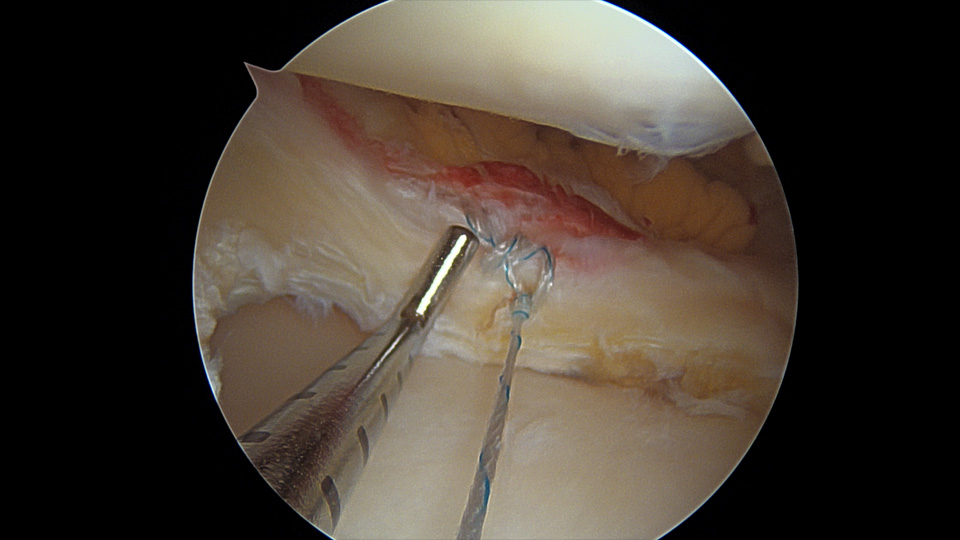

관절경 수술 소견에서 파열된 연골판을 봉합한다.

- 환자 동의하에 게시된 이미지입니다.